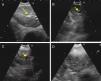

Presencia de una densidad hiperecogénica en el interior del GL (figs. 1 y 2).

Figura 1.Series de imágenes ecográficas de EBUS de ganglio linfático mediastínico que muestran diferentes criterios. A)Ecogenicidad heterogénea con margen bien delimitado en ganglio linfático reactivo. B)Ecogenicidad homogénea con margen mal definido en linfadenitis reactiva. C)Ecogenicidad heterogénea con margen bien delimitado en adenocarcinoma. D)Densidad hiperecogénica en el interior de ganglio linfático (flecha) en carcinoma microcítico. Las imágenes de ganglios linfáticos (A-D) mostraron ausencia de estructura hiliar central.